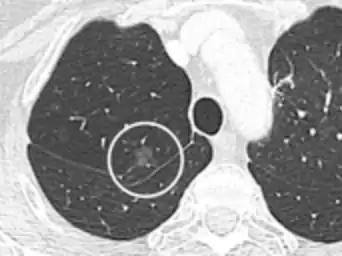

CT image showing ground-glass nodule (circled).

Pre-malignant or malignant causes of nodular GGOs include adenocarcinoma, adenocarcinoma in situ, and atypical adenomatous hyperplasia (AAH). One large review study found that 80% of nodular GGOs which were present on repeated CT imaging represented either pre-malignant or malignant growths. Differentiating between pre-malignancy and malignancy on the basis of CT alone can pose a challenge to radiologists; however, there are several features that are indicative of pre-malignant nodules. AAH is a pre-malignant cause of nodular GGO and is more commonly associated with lower attenuation on CT and smaller nodule size (<10 mm) compared to adenocarcinoma.[10] In addition, AAH often lacks the solid features and spiculated appearance that are often associated with malignant growths.[9] In contrast, as adenocarcinoma becomes invasive it will more often cause retraction of adjacent pleura and may show an increase in vascular markings. Nodules >15 mm almost always represent an invasive adenocarcinoma.[9][10]